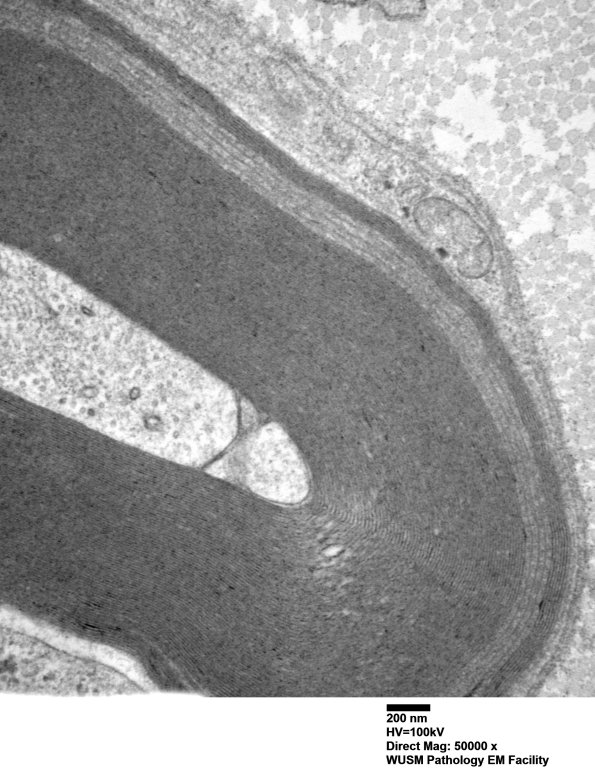

Washington University Experience | PERIPHERAL NEUROPATHY | 12 ANTI-MAG NEUROPATHY | 9C2C (Case 9) Nerve_027 - Copy

Other examples of WSM were encountered and were more compelling in this case. (electron micrographs)